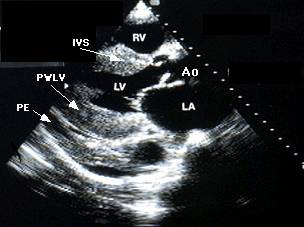

Ecocardiografia permite evaluarea afectarii functiei contractile, excluderea unor boli valvulare sau pericardice. Se apreciaza forma si functia VS (tipic VS globulos cu functie contractila global alterata), gradul insuficientelor valvulare, prezenta trombozei intracavitare (intraatriala sau intraventriculara). Cresterea dimensiunilor cavitatilor stangi si drepte este progresiva cu cresterea clasei functionale NYHA. Producerea emboliilor se asociaza cu dimensiunea VS si fractia de ejectie (FE).

Ecocardiografia si angiografia cu radionuclizi (ARN) evidentiaza dilatatia si hipokinezia sau diskinezia difuza a VD.